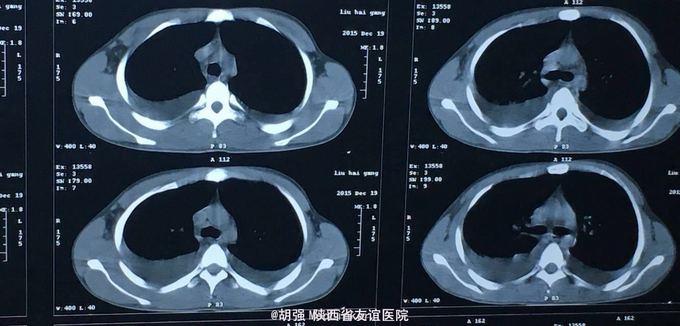

查体:口唇无发绀,咽充血,双侧扁桃体2度大,表面可见脓胎。两肺呼吸音粗糙,可闻及管状呼吸音。余查体无明显异常。 辅助检查:血常规提示白细胞及血小板明显低于正常值,肝功提示转氨酶升高。凝血系列:PT、APTT时间明显延长。T sport试验弱阳性。10月份胸部CT平扫未见明显异常。10月26日及12月12日胸片未见明显异常。12月19日胸部CT提示:两肺斑片状阴影,两侧胸腔积液。